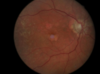

Dry Macular degeneration

what is this?

age?

2 key findings?

tx considerations? 3 things

painless and progressive CENTRAL vision loss, OVER 50

FINDINGS:

- drusen-small yellow deposits lead to degenerative changes and atrophy

- changes on amsler grid

TX:

AREDS trial-tx with high antioxidants plus zinc can reduce up to 25%

(b-caretene, vit C, E, zinc)

Wet macular degeneration

what are the two things the contribut to this?

patho?

2 findings?

1 tx?

neovascular (new growth) and exudative (hemmorage), 10% of those with macular dengen but 90% of blindness

patho: subretinal fluid accumulation from neovascularization or fragile vessels that rupture

FINDINGS:

- metamorphopsia-hemmorage causing wavy and distorted vision with paracentral scotomas “blind spots”

TX: ANTI-VEGF (vascular endothelial growth factor), 9/10 stabilize